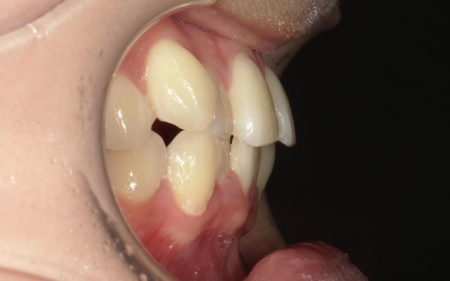

20代女性 八重歯と歯並びの乱れをマウスピース矯正装置で改善した症例

「上下の八重歯が気になる」とご相談いただきました。

拝見したところ、歯が正しく並ぶためのスペースが不足しており、歯が重なって生えてしまう叢生(そうせい)の状態が全体的に見られました。

特に上下の糸切り歯が外側にずれている、いわゆる八重歯が目立っています。